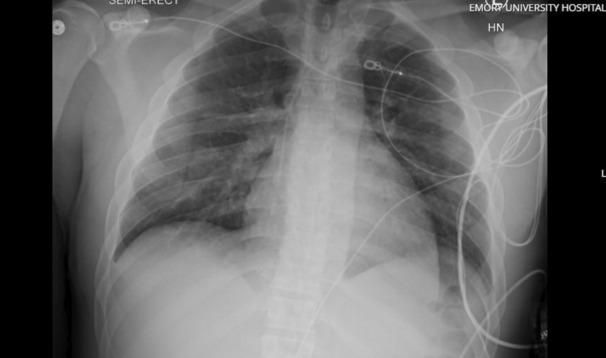

Negative pressure pulmonary edema (NPPE) may result in respiratory failure refractory to conventional management strategies. Venovenous extracorporeal membrane oxygenation (VV ECMO) can serve as a rescue therapy in cases of severe respiratory failure. Rapid initiation of VV ECMO can decrease morbidity and mortality while facilitating early liberation from mechanical ventilation and promoting early rehabilitation. We describe the successful utilization of VV ECMO as rescue therapy for severe NPPE-induced hypoxic respiratory failure and peri-arrest state in the postanesthesia care unit (PACU) in a patient with postextubation airway obstruction after undergoing patellar tendon repair.

负压性肺水肿(NPPE)可能导致对传统治疗策略无效的呼吸衰竭。静脉-静脉体外膜肺氧合(VV ECMO)可作为严重呼吸衰竭病例的一种挽救治疗方法。快速启动VV ECMO可降低发病率和死亡率,同时有助于早期脱离机械通气并促进早期康复。我们描述了在一名接受髌腱修复术后拔管后气道梗阻的患者中,成功将VV ECMO用作麻醉后护理单元(PACU)中严重NPPE引起的低氧性呼吸衰竭和濒死状态的挽救治疗方法。